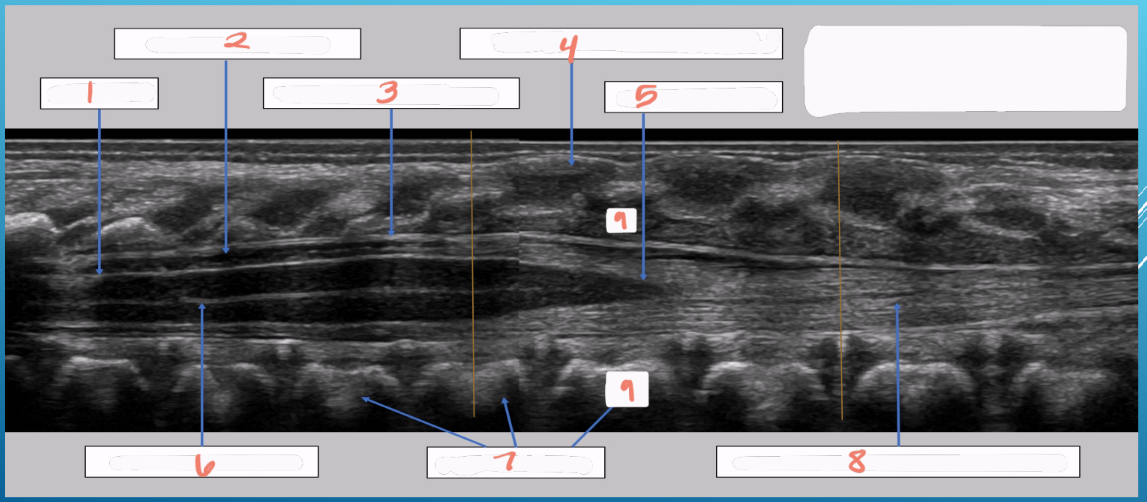

1

subarachnoid space

2

cartilaginous spinous processes

3

dura mater

4

epidural space

5

central echo complex in hypoechoic spinal cord

6

conus medullaris

7

vertebral bodies